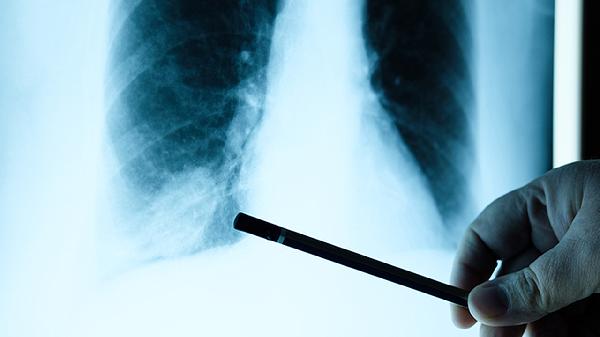

针对骨转移引起的局部疼痛,精准放疗如三维适形放疗可有效破坏肿瘤细胞。对于多发性骨转移可采用放射性核素治疗。放疗后可能出现骨髓抑制等副作用,需配合血常规监测。该疗法起效时间约1-2周,镇痛效果可持续数月。